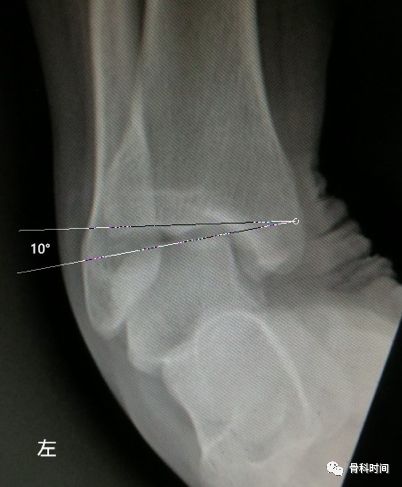

生活中,崴脚后常常忽视外固定的作用,特别是未存在撕脱骨折以及 X 线片假阳性者,踝关节应力位 X 片对于单纯的韧带损伤可发现踝关节不稳。

距骨倾斜角:内翻应力正位片中距骨相对于胫骨远端关节面倾斜角度≥9°,即可考虑踝关节不稳,但此时应考虑患者的职业,如芭蕾舞演员可存在足踝部韧带松弛

28 岁青年女性,约 2 年前左踝首次发生崴脚,未行外固定处理,近 1 年来左踝间断多次崴脚,双侧踝关节应力正位片测量距骨倾斜角,左侧为 10°,右侧 4°,左侧应力位状态下感疼痛,右侧无不适感,考虑左侧踝关节不稳。